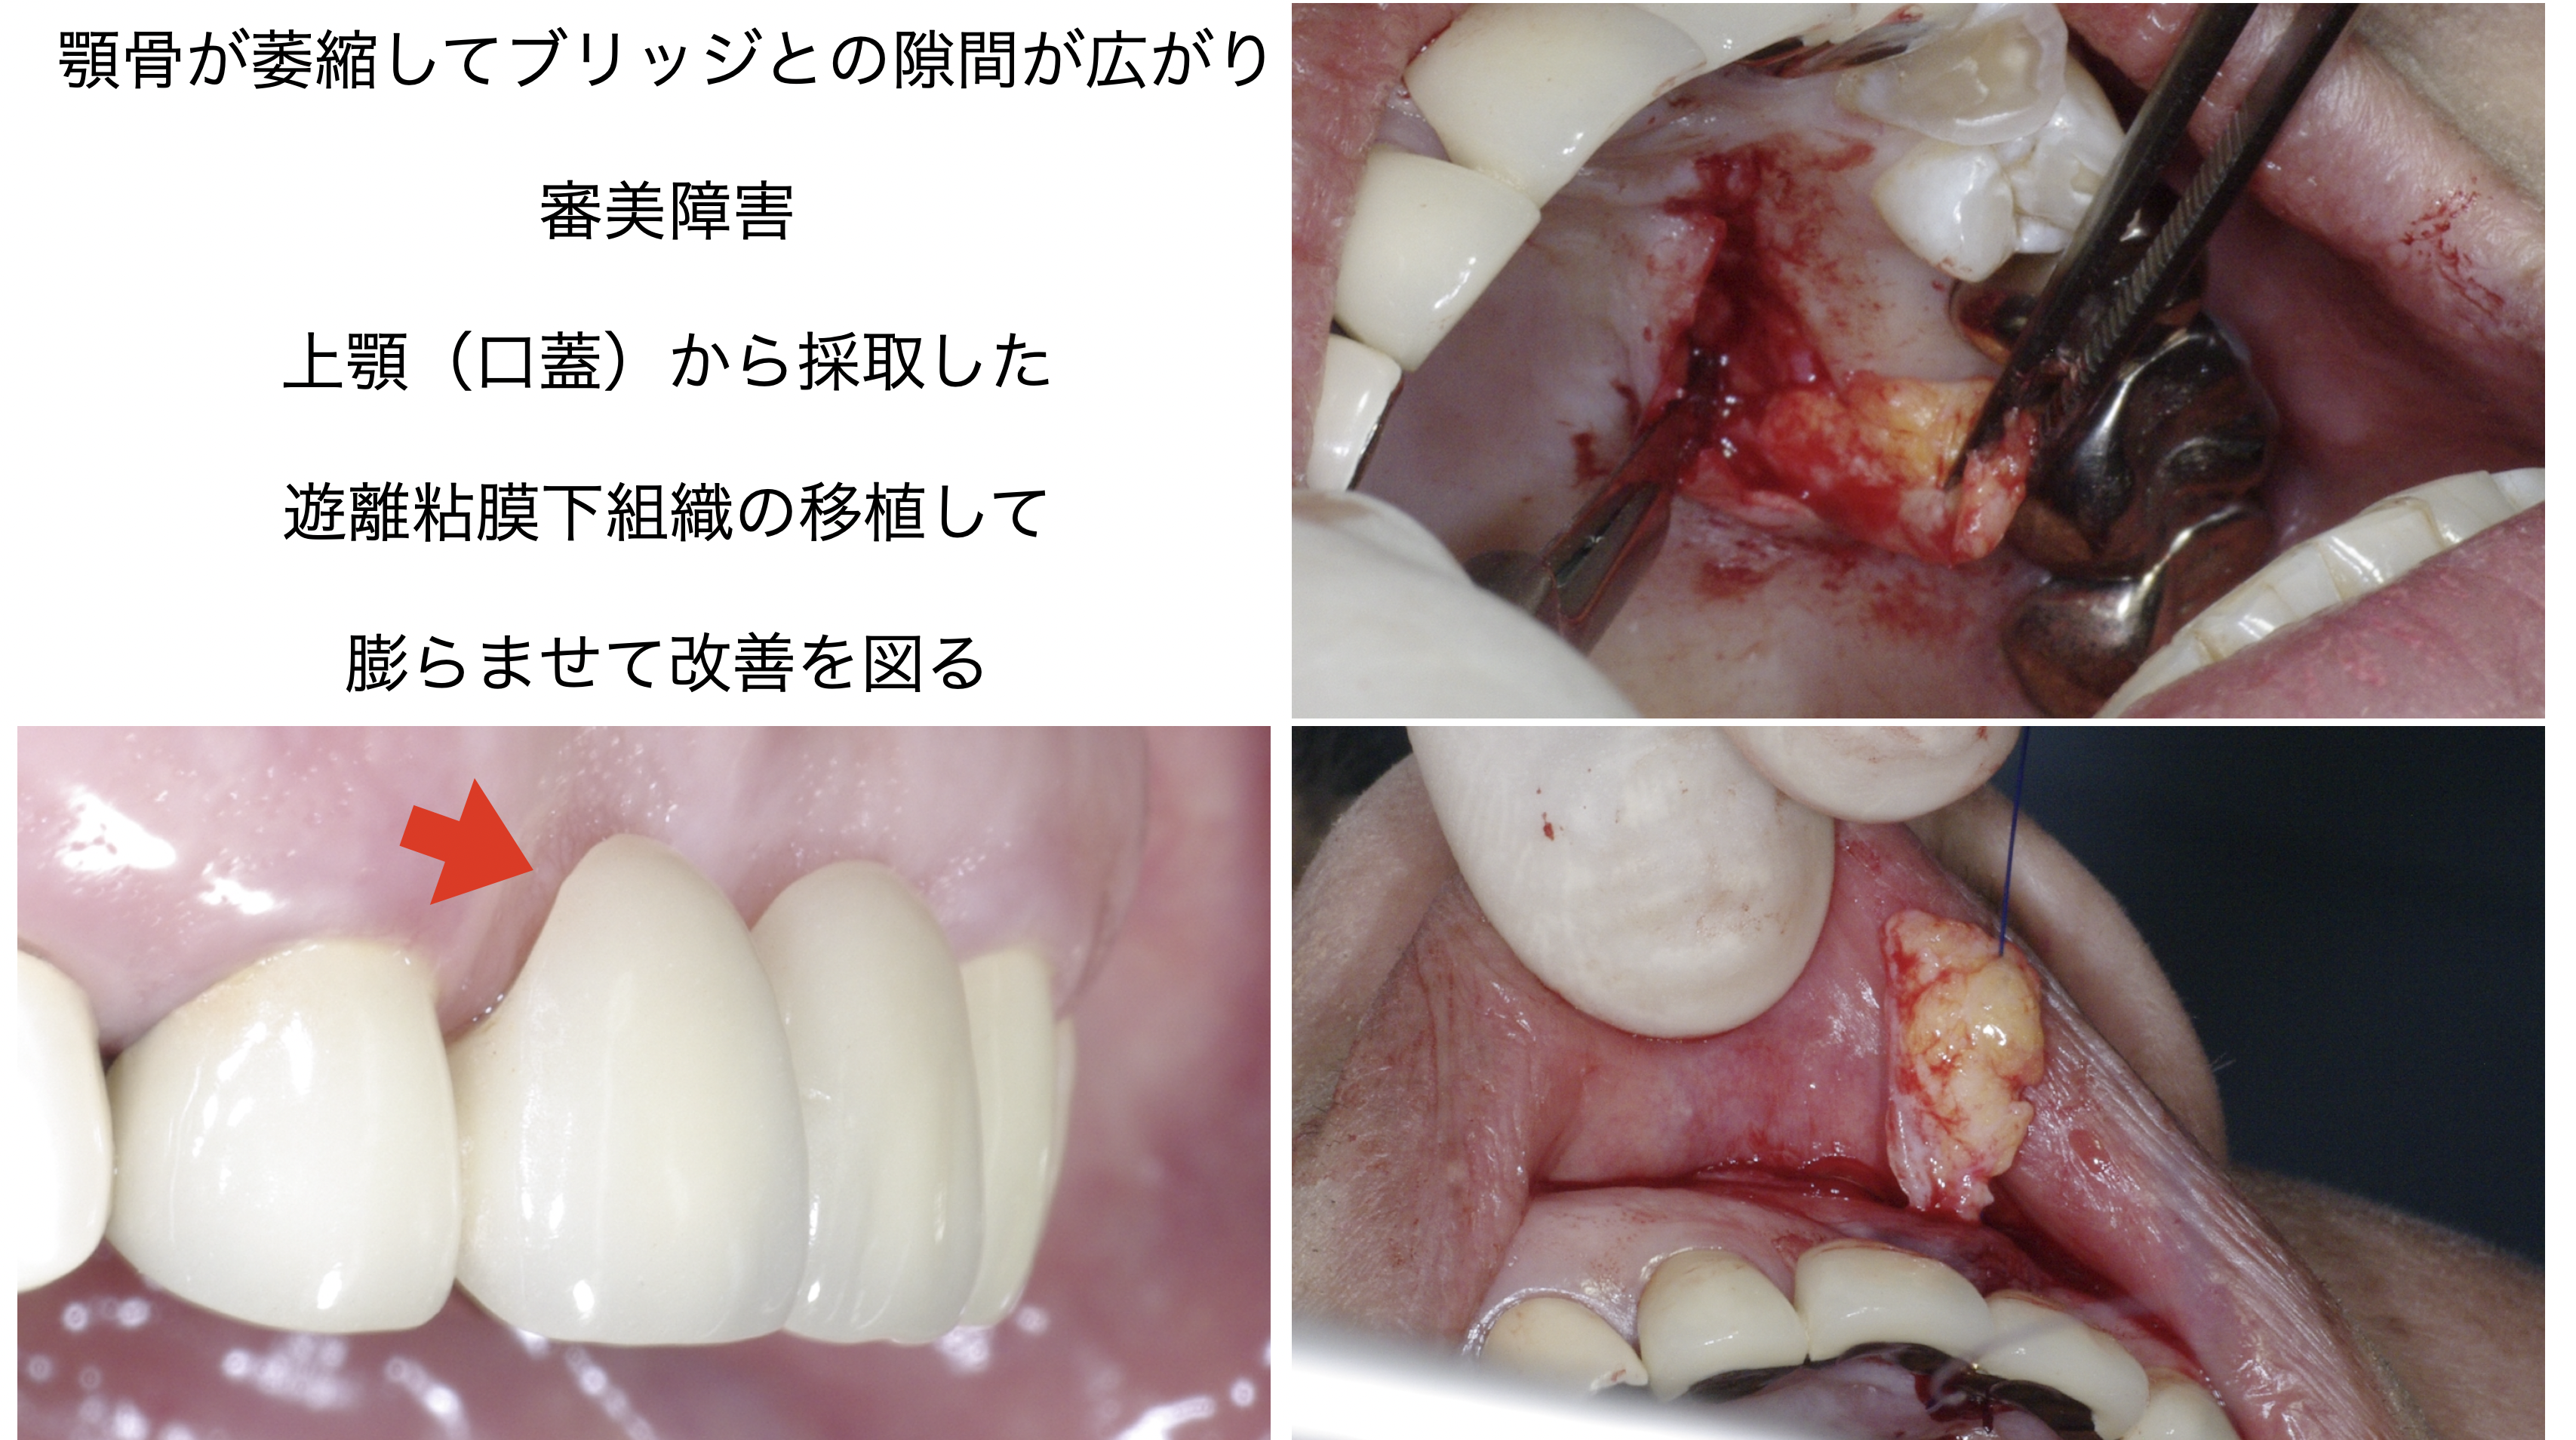

補綴前外科処置、歯冠延長術、遊離粘膜移植術、遊離粘膜下組織移植術など

遊離粘膜下組織移植術は軟組織でボリュームの回復を図る処置です。

遊離粘膜下組織移植術は軟組織でボリュームの回復を図る処置です。